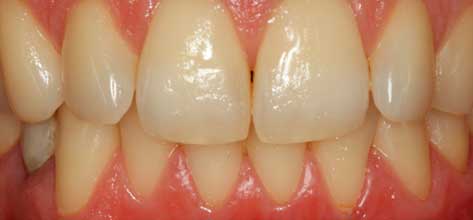

En este caso se combinan dos tratamientos el blanqueamiento y la carilla. La paciente tratada con blanqueamiento y carilla de composite a nivel de un incisivo central para mejorar el color y cerrar el diastema existente

Dra. Carmen Feito Bárcena

Blanqueamiento y carillas